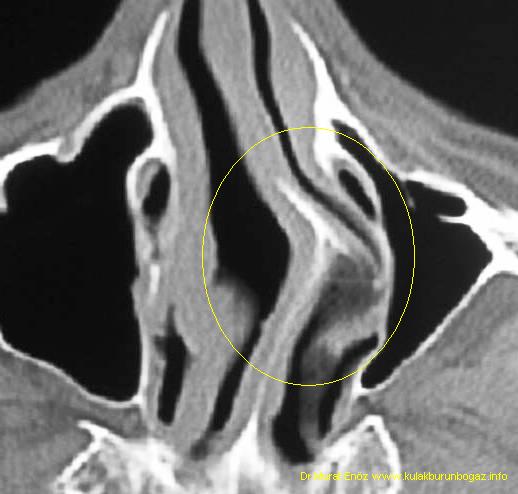

The nasal septum is the thin wall of bone and cartilage that separates the right. If you're searching for something that will make a big difference in the quality of your sleep, or just help your snoring so you're not a intense sleeper on those long. Your breathing at night would be no better or no worse than it is at any other time of day due to the deviated septum.